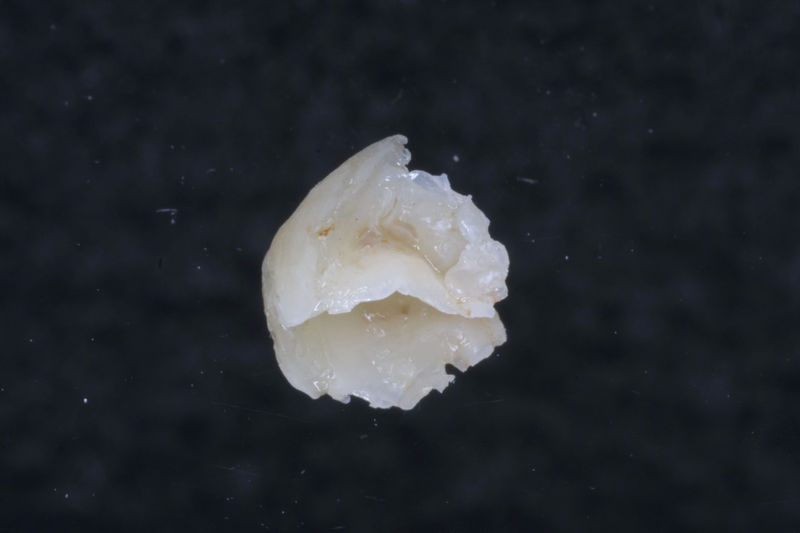

Son aditamentos artificiales colocados en la parte interna de la raíz de dientes con tratamiento endodóntico y con amplia destrucción. Usados comúnmente para soportar coronas completas.